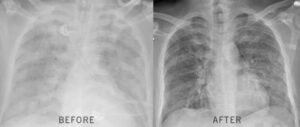

Within 17 days, the stuntman went from planning his funeral to riding 12 miles on horseback. His FEV1 jumped 31%. The rapper went from cutting sessions short to recording for hours without his inhaler. Their doctors were stunned.